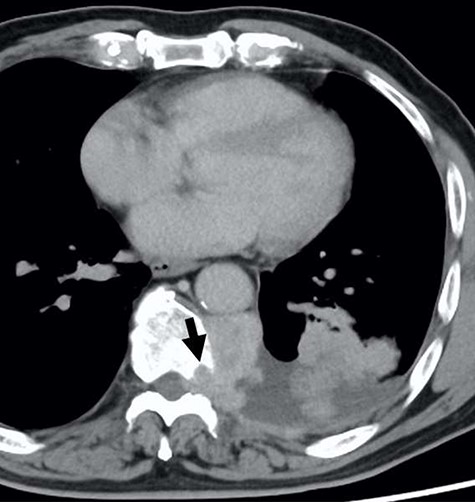

A 78-year-old man complained of chest pain for 2 months and was admitted to our hospital. Computed tomography (CT) scans revealed a tumor in the left thorax. He had undergone prior surgical resection of the primary SFT and recurrent tumor at 11 and 2 years before the current presentation. The CT findings of the primary tumor revealed a solitary, well-circumscribed and no signs of invasion (Fig. 1). Intraoperatively, the primary tumor arose from the visceral pleura and the resection was performed by wedge resection. The resected tumor was an oval, elastic soft mass with homogenous milky white cut surfaces. Postoperative histopathologic and immunohistochemical findings were consistent with SFT, and the mitosis and malignant features, including nuclear atypia, necrosis or higher cellularity, were hardly seen. In contrast to the primary tumor, as shown in Fig. 2, the CT findings revealed that the current tumor extended through the neural foramen. Furthermore, the tumor had an osteoclastic progression into the thoracic spine. Therefore, this tumor was considered to become malignant, and we considered the surgical complete resection is impossible. For histological confirmation, CT guided needle biopsy was performed. The histological findings of this recurrent tumor were identical to those of the primary tumor. The mitosis was hardly seen in this recurrent tumor. However, immunohistochemically, the MIB-1 proliferation index (Ki-67) of the primary tumor and the current tumor was 1.74 and 30.00%, respectively (Fig. 3A and B).

The computed tomographic findings of the current tumor; note the tumor extended through the neural foramen, and had an osteoclastic progression into the thoracic spine (arrow).